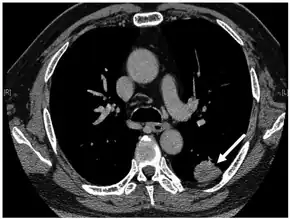

.png.webp)

- Carcinomas

- Lung cancers (small-cell lung cancer, mesothelioma)

- Gastrointestinal cancers (stomach, duodenum, pancreas)

- Genitourinary cancers (bladder, urethral, prostate, endometrial)

- Lymphoma

- Sarcomas (Ewing's sarcoma)